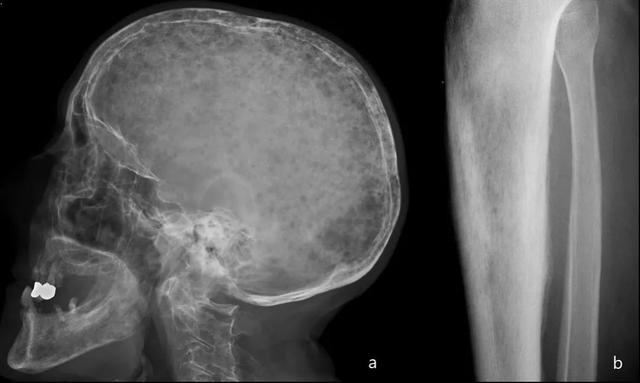

多发性疾病(65%)比单一性疾病更普遍。最常见的受累部位是骨盆,脊柱,头骨和近端长骨。

在头骨中,更常见的发现是剪纸画样的骨质疏松(大,明确的裂解病变),板障扩大和姚蜜昂样形态(混合溶解和硬化病变)。

长骨:草叶或蜡烛火焰标志:开始作为透明度的软骨下区域,具有V形骨溶解的前端,向骨干延伸。

骨闪烁显示疾病的所有阶段的摄取显着增加(图20)。

图20:患者病程10年。颅骨的侧位X线片(a):颅骨中大的明确的溶解病变,内颅骨表和外颅骨表都涉及(局限性骨质疏松)。胫骨的侧位X线照片(b):具有V形前端的透明度的软骨下区域骨溶解,向骨干延伸。除图像外,血清碱性磷酸酶(ALP)和尿羟脯氨酸升高证实了Paget病在裂解阶段。